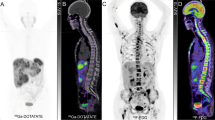

SPECT versus PET imaging protocols

Both [123I]MIBG and [111In]pentetreotide scintigraphy are well-established modalities for staging and restaging as well as the follow-up of PPGLs. SPECT/CT has now become more widely available and offers the advantage of sequential acquisition of both morphological and functional data, thus increasing diagnostic confidence in terms of image interpretation and disease localisation, while enhancing sensitivity. These techniques are associated with some constraints, including prolonged imaging, relatively prolonged uptake times prior to imaging, and the presence of some gastrointestinal tract artefacts necessitating bowel cleansing, thyroid blockade, or temporary withdrawal of certain drugs that can interfere with appropriate image interpretation. The low resolution of conventional SPECT imaging can also limit the detection of small lesions. In addition, SPECT does not provide a quantitative estimate of tumour uptake, and quantitative SPECT/CT is not widely used in the clinic. Accordingly, the use of PET imaging has been increasing because of some technical as well as clinical advantages over SPECT. Currently, [18F]FDG is the most accessible tracer and plays an important role in the evaluation of these tumours, particularly SDHx-related PPGLs [55, 140]. [18F]FDOPA is also available, albeit in only a few countries. Furthermore, it is not yet approved by the Food and Drug Administration for use in the USA. Nevertheless, it is a sensitive radiotracer for the evaluation of sporadic and some metastatic PPGLs. Other tracers such as [18F]FDA and [11C]HED, which are very specific for chromaffin/ganglionic cells, are unfortunately not available at most centres and not approved by the Food and Drug Administration. Because of recent and excellent results obtained with PET imaging using various [68Ga]SSAs for patients with hereditary and non-hereditary PPGLs, [68Ga]DOTATATE is approved by the Food and Drug Administration while [68Ga]DOTATOC is approved by the EMA for the evaluation of PPGLs and GEP NETs, respectively. Both of these are now in use worldwide (Table 2).

Recommendations for clinical practice according to different clinical scenarios

Successful PPGL management requires an interdisciplinary team approach. Precise identification of the clinical context and genetic status of patients enables the personalised use of functional imaging modalities [4, 140, 157,158,159] (Table 3). Since the European Association of Nuclear Medicine 2012 guidelines were issued, the excellent results obtained with [68Ga]DOTA-SSAs have simplified the imaging approach for PPGL patients [160].

Metastatic PPGLs